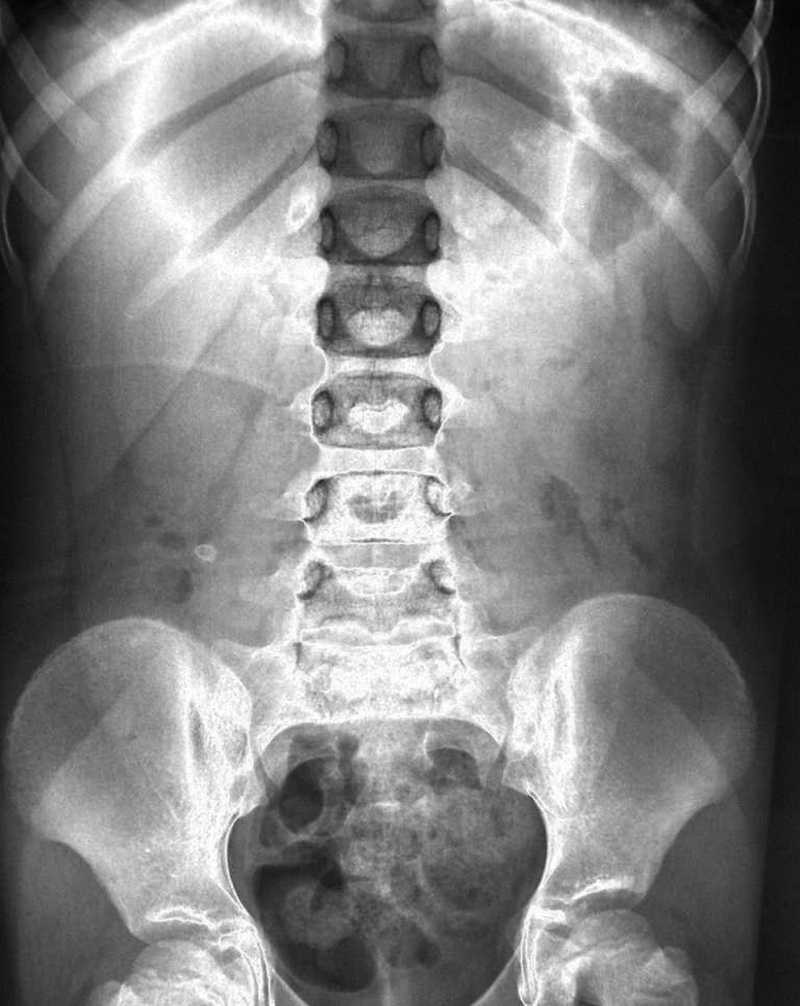

Este procedimiento fue empleado en las radiografías de manera limitada. Diferentes autores lo aplicaron para intensificar los contornos de las trompas de Falopio o para ilustraciones que aumentaban los riñones y los uréteres. También se utilizó para la visualización de la forma de los huesos de la nariz, la rodilla o para algunas estructuras óseas más finas, como la articulación temporomandibular o la porción petrosa del hueso temporal, al producir una mayor prominencia a través del bajorrelieve. Incluso, se publicó un artículo sobre las radiografías en bajorrelieve que ilustraba su uso en el tracto gastrointestinal y en las radiografías de tórax (fig. 2). Eubank, en 1953, presentó una relieve-mamografía mediante la que se ponía en relieve el sistema ductal de la mama4.